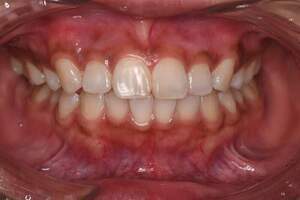

歯石除去

治療前

治療後

| 年齢 | 36歳・男性 |

| 主訴 | 歯石をとりたい |

| 治療内容 | 歯石除去 |

| 治療期間 | 30分 |

| 費用 | 約2,000円 |

| リスク・副作用 | ・歯ぐきの炎症が強いと歯石を取る際に出血することがあります。 ・処置後に歯がしみることがあります。 ・歯と歯の間に隙間ができるので、息が漏れ発音しにくいと感じることがあります。 ・歯ぐきの炎症が軽減すると歯ぐきが引き締まり、歯が長く見えることがあります。 |